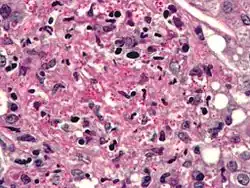

Infecting C. neoformans cells are usually phagocytosed by alveolar macrophages in the lung.[11] The invading C. neoformans cells may be killed by the release of oxidative and nitrosative molecules by these macrophages.[12] However some C. neoformans cells may survive within the macrophages.[11] The ability of the pathogen to survive within the macrophages probably determines latency of the disease, dissemination and resistance to antifungal agents. In order to survive in the hostile intracellular environment of the macrophage, one of the responses of C. neoformans is to upregulate genes employed in responses to oxidative stress.[11]

The haploid nuclei of C. neoformans can undergo nuclear fusion (karyogamy) to become diploid. These diploid nuclei may then undergo meiosis, including recombination, resulting in the formation of haploid basidiospores that are able to disperse.[13] Meiosis may facilitate repair of C. neoformans DNA in response to macrophage challenge.[13][14]